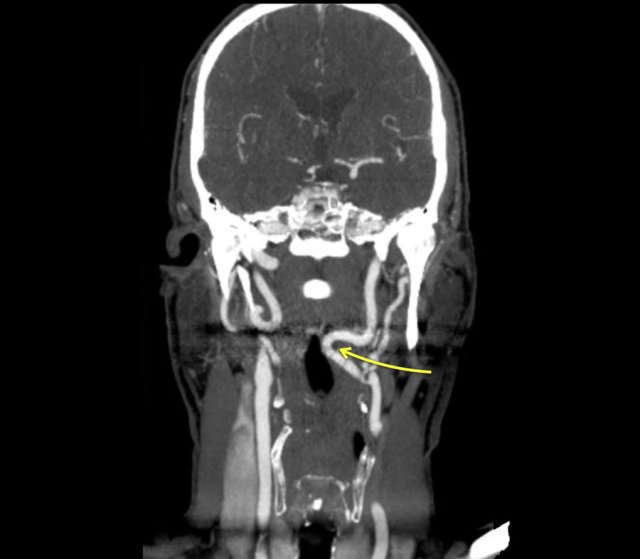

The CT image shows that the smooth indentation of the oropharynx on the right was caused by an elongated internal carotid artery.

So indeed this is an uncommon case in which on the fluorographic study a tumor was suspected in the pyriform sinus.

Finally a proces was found within the oropharynx and a proces compressing the wall from outside at a higher level.

Due to these processes there was an asymmetric passage of contrast in the hypopharynx simulating a proces in the pyriform sinus.

Here another patient with an elongated internal carotid artery.

This patient had swallowing problems and at inspection a pulsating structure was seen in the oropharynx.

This is not un uncommon finding.

So before you perform a biopsy in this area make sure that you are not dealing with the carotid artery.